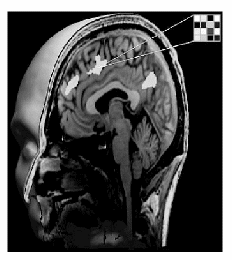

bild

Abb. l Neuere Auswertverfahren suchen nicht nach einzelnen Bildpunkten, welche möglichst gut mit dem experimentellen Design korrelieren, sondern überprüfen räumlich verteilte Bildpunkte auf spezifische Zusammenhänge ihrer Aktivierung, das Muster.

Auch wenn die Hirnforscher nicht unter den ersten Plätzen des „Brain Interpretation"-Wettbewerbs vertreten waren, bewegt sich doch einiges an der Forschungsspitze der kognitiven Neurowissenschaft, um die neuronalen Grundlagen von Denkprozessen zu verstehen. Neuere multivariate Auswertmethoden beschränken sich nicht darauf, gemittelte Signalstärke einzelner Voxel oder Regionen auf ihre Korrelation mit einem Stimulus oder einer Aufgabe zu untersuchen. Stattdessen suchen sie in Gehirnaufnahmen einer bestimmten Zeitspanne nach spezifischen Mustern aktivierter Voxel in einem bestimmten Hirnbereich. Diese Ergebnisse können dabei helfen, ungelöste Fragen der neuronalen Informationsverarbeitung zu lösen, beispielsweise ob diese eher modular und lokal funktioniert (27, 28) oder holistisch und räumlich verteilt (29, 30). Die Verfahren, die dabei zum Einsatz kommen, werden schon bei zahlreichen praktischen Anwendungen zur Mustererkennung verwendet, etwa der automatischen Gesichtserkennung oder der Analyse von DNA Information. Dabei funktionieren die Auswerteprogramme, zum Beispiel die „Support Vector Machines" (SVM) (31, 32), nach dem folgenden Verfahren: Zunächst sucht der Algorithmus mit einer Reihe von Trainingsdatensätzen nach Zusammenhängen in der Aktivierung der einzelnen Datenpunkte, dem Muster. Dafür muss man jedoch nicht nur die Datenpunkte selbst, sondern auch Information darüber in das System füttern, welche experimentelle Bedingung zu welchen Daten gehört. Ist die Trainingsphase abgeschlossen, verwendet man idealerweise einen neuen Datensatz, um die Klassifikation des Algorithmus zu überprüfen. Hat dieser für bestimmte Datenpunkte ein Muster erkannt, wird er mit einer gewissen Wahrscheinlichkeit bestimmen können, welche experimentelle Bedingung bei der Aufnahme dieses Datensatzes vorlag. Gelingt das mit hoher Genauigkeit, so kann man darauf schließen, dass das Muster der neuronalen Verarbeitung an diesem Ort, über mehrere Datenpunkte verteilt, spezifisch mit der experimentellen Aufgabe verbunden ist (Abb. 1).